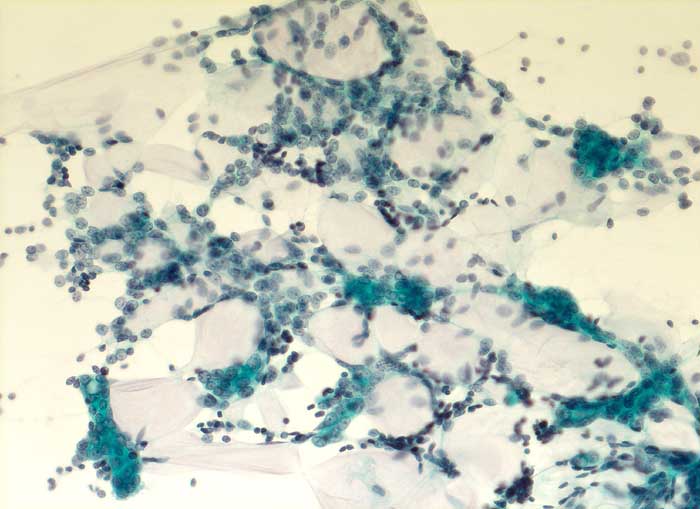

Adenoidzystisches Karzinom der Mamma

Adenoidzystische Karzinome machen lediglich 1% aller Mammakarzinome aus. Die Morphologie ist identisch mit dem gleichnamigen Tumor der Speicheldrüsen. Die Zellen des adenoidzystischen Karzinoms bilden kohäsive Verbände und Drüsen oder mikrozystische Strukturen. Die Tumorzellen sind klein und monomorph, die Kern-Zytoplasmarelation ist hoch. Die Kerne sind dunkel, rund bis oval oder angulär und enthalten bisweilen einen kleinen Nukleolus. Azelluläre hyaline Körperchen aus mucoidem Material, welche die Hohlräume der intakt aspirierten kribriformen Strukturen ausfüllen, sind besonders typisch. Das mucoide Material kann auch verzweigte oder fingerartige abgerundete Strukturen ausbilden.